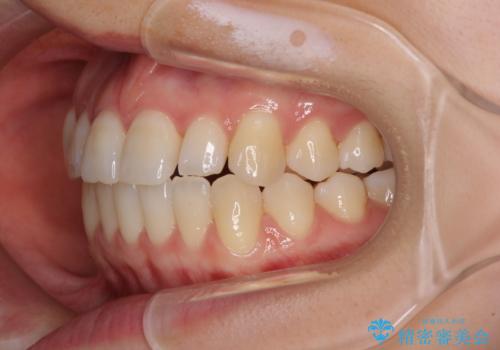

前歯のクロスバイト インビザラインによる矯正治療

- 前歯のクロスバイトを気にして来院された患者様です。

短期間での治療を希望され、ワイヤー装置とインビザラインとで悩んでいましたが、自己管理を徹底すると言うことでインビザラインによる矯正治療を行うこととしました。

しっかりとインビザラインの装着時間を守っていただいたので、1年弱で矯正治療を終えることができました。